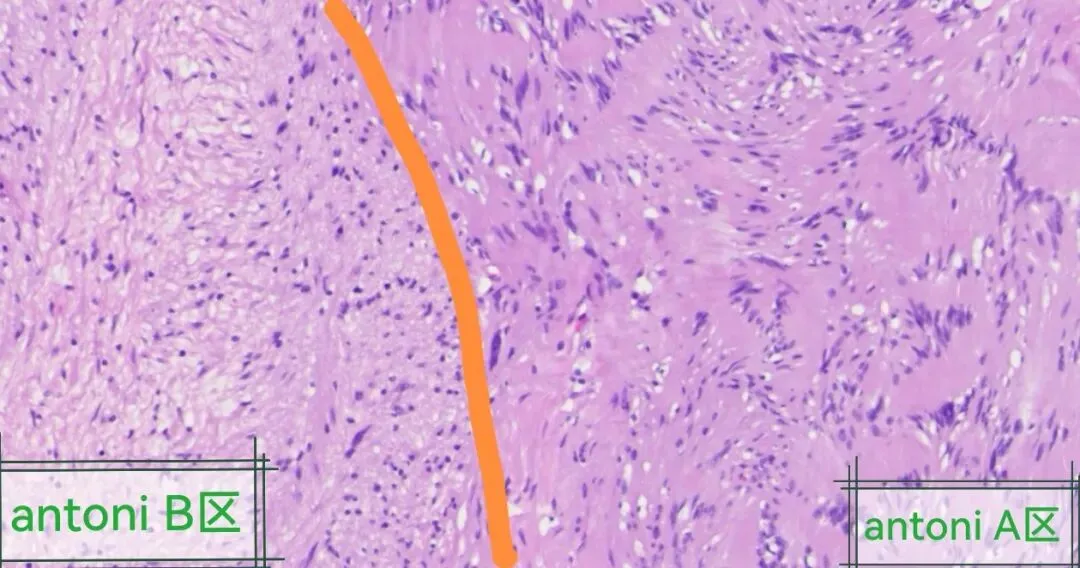

好似神经鞘瘤的antoni A区和antoni B区,但又不是太典型,典型图片如下:

1.Antoni A型:瘤细胞密集,核排列成与细胞长轴垂直的栅栏状结构,称为Verocay小体,胞突和基底膜红染。

2.Antoni B型结构表现为疏松网状背景,细胞成分少,肿瘤细胞核小,呈卵圆形。黄色瘤细胞常见。

3.构成肿瘤的神经鞘细胞胞质丰富,淡伊红染色,细胞边界不清,核呈长梭形,两头顿,大小同平滑肌细胞。